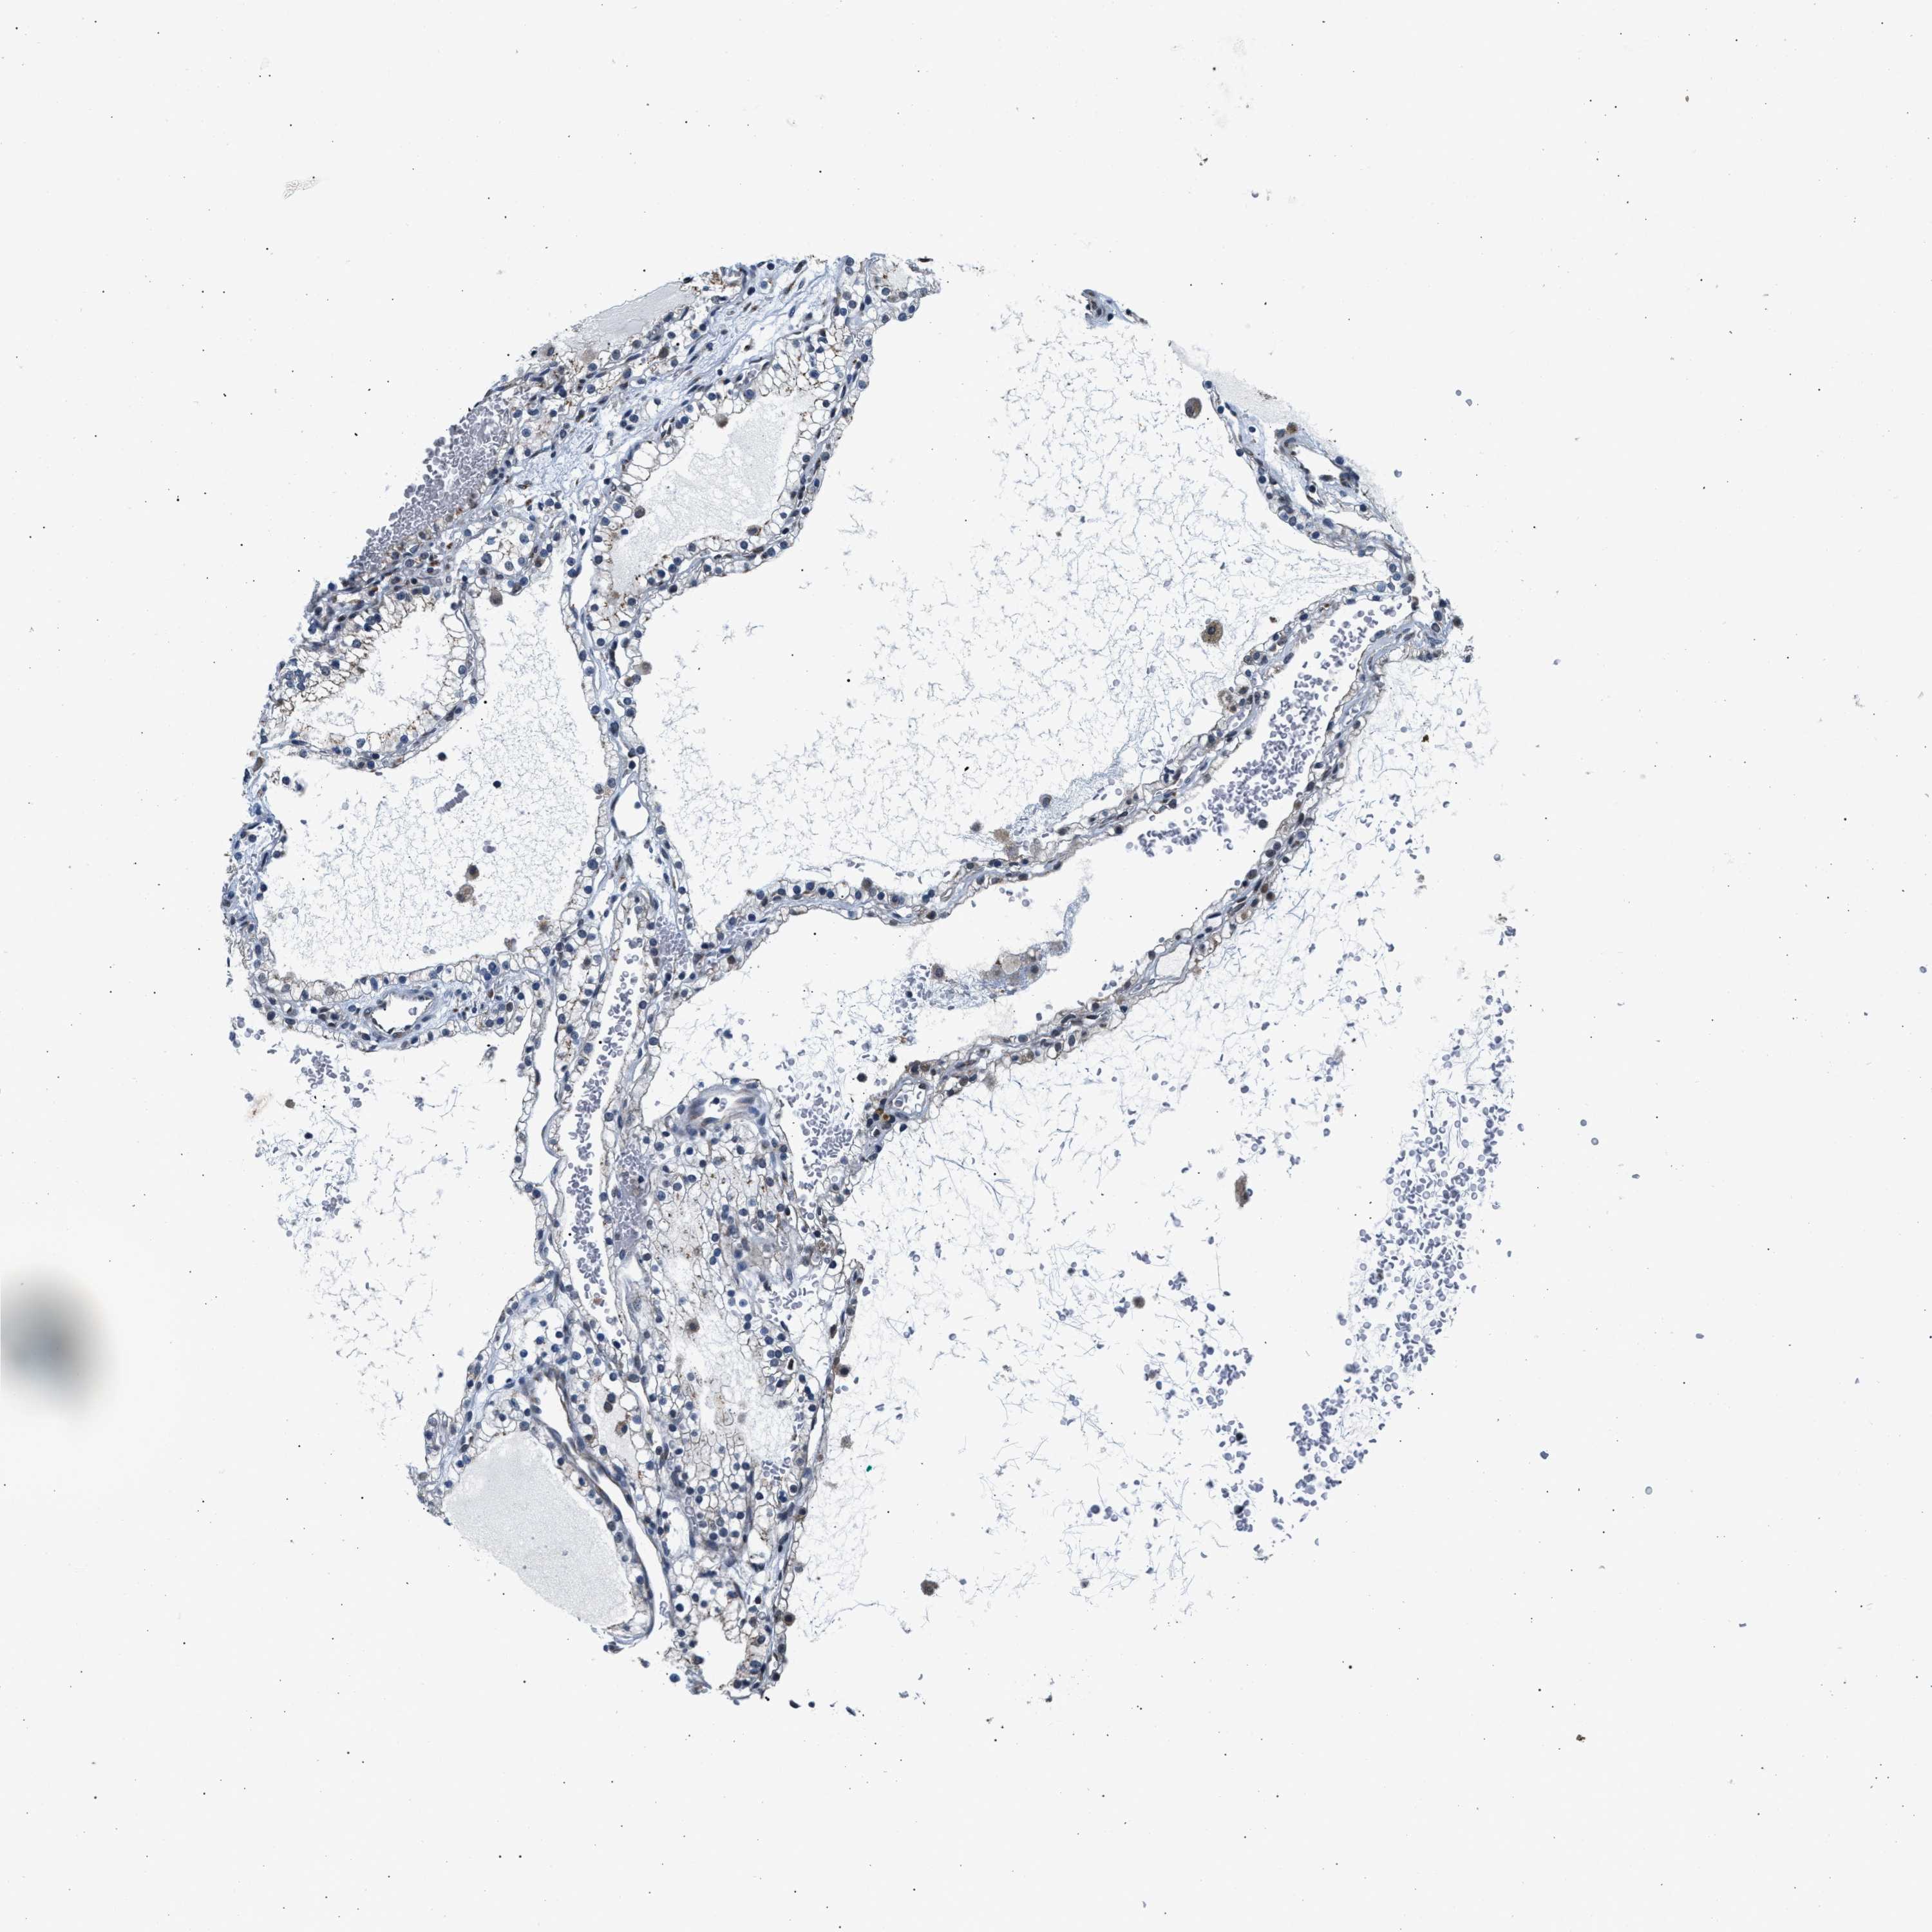

TCGA RNA samplesi

RNA-seq data is reported as average FPKM (number Fragments Per Kilobase of exon per Million reads), generated by the The Cancer Genome Atlas (TCGA) .

Normal distribution across the dataset is visualized with box plots, shown as median and 25th and 75th percentiles. Points are displayed as outliers if they are above or below 1.5 times the interquartile range. FPKM values of the individual samples are presented next to the box plot.

Average pTPM 0.6

Number of samples 100